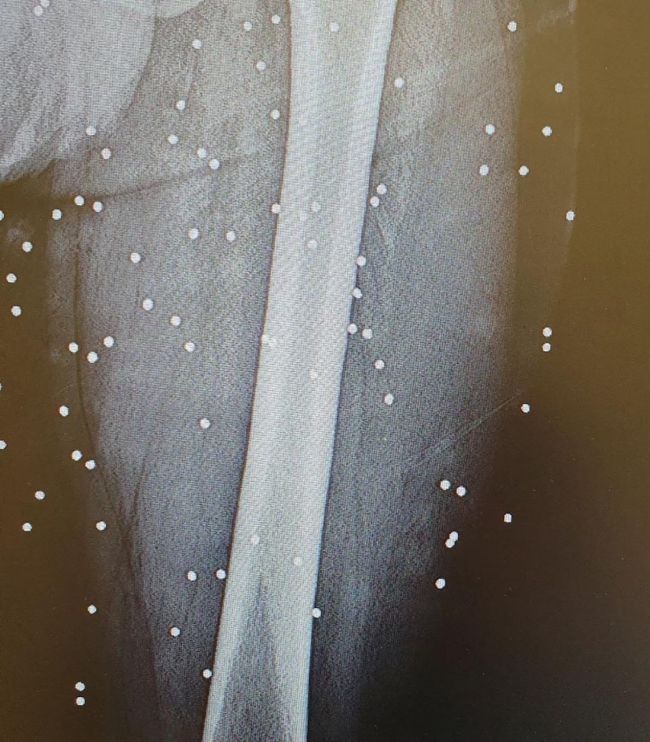

«مدرک جرم»؛ گلوله جنگی و ساچمه در بدن مردم به روایت عکسهای رادیولوژی بیمارستانهای مشهدشهرام سدیدی، شاعر و زندانی سیاسی سابق ساکن لندن، تصاویری از عکسهای رادیولوژی بیمارستان «امام رضا» مشهد را منتشر کرده است که در آنها، آثار گلولههای جنگی و ساچمه در بدن مجروحان انقلاب ملی دیده میشود.

سدیدی با انتشار این تصاویر در اینستاگرام، آنها را «سند کوچکی از جنایات» جمهوری اسلامی «با مردم شریف ایران» توصیف کرد.

شهرام سدیدی، شاعر و زندانی سیاسی سابق ساکن لندن، تصاویری از عکسهای رادیولوژی بیمارستان «امام رضا» مشهد را منتشر کرده است که در آنها، آثار گلولههای جنگی و ساچمه در بدن مجروحان انقلاب ملی دیده میشود.

سدیدی با انتشار این تصاویر در اینستاگرام، آنها را «سند کوچکی از جنایات»… pic.twitter.com/S89ELP93af